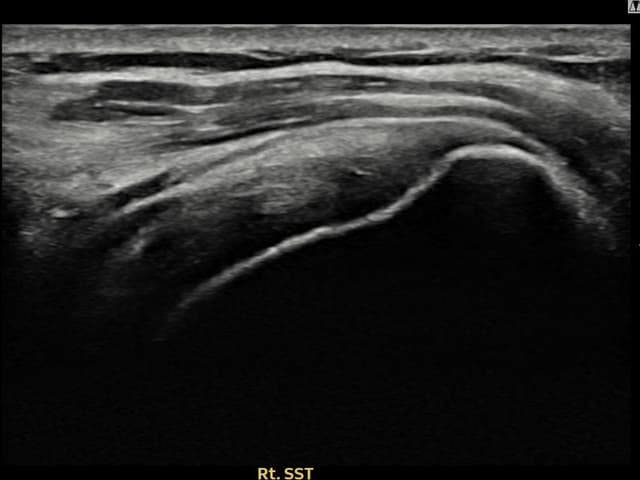

右侧 冈上肌腱 石灰化肌腱炎

10mm × 7mm